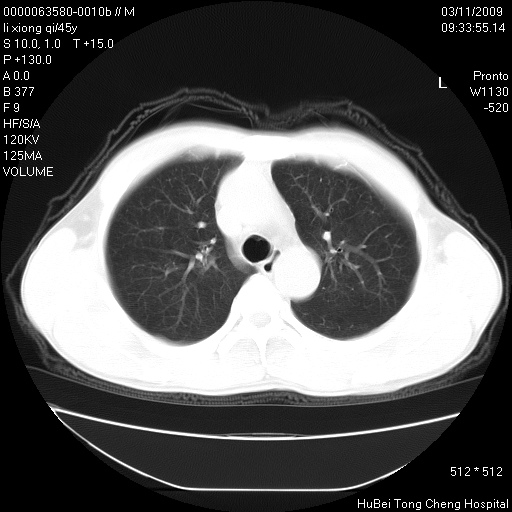

患者 男,45岁。胸痛,咳嗽伴痰中带血1月余。

临床诊断:肺结核?

胸部ct轴位平扫(层厚10mm,螺距1.5,重建间隔10mm),图像如下:

考虑肝癌肺转移

考虑肝癌肺转移。

肝癌肺转移